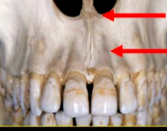

what can you say about the surface anatomy of the maxilla around the teeth themselves?

very undulating - prominences over roots

bony spike of the anterior nasal spine

this increased radiopacity is caused by the soft tissues at the tip of the nose - shadow - dense tissue